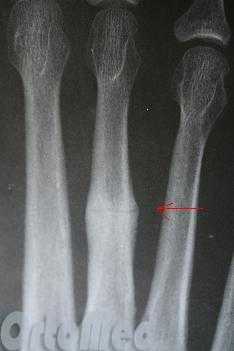

(Справа) Пациент, у которого развилась остеопения вследствие снижения двигательной активности. При рентгенографии стопы в передне-задней проекции визуализируются небольшая ступенеобразная деформация и ограниченная периостальная реакция на уровне стресс-перелома 3-й плюсневой кости. При рентгенографии, выполненной двумя неделями ранее, изменения отсутствовали.

• Стресс-перелом, как правило, характеризуется отсутствием смещения отломков:

о Сразу после травмы (на момент дебюта болевого синдрома) перелом может не визуализироваться

о Через 7-10 дней может визуализироваться ограниченная периостальная реакция